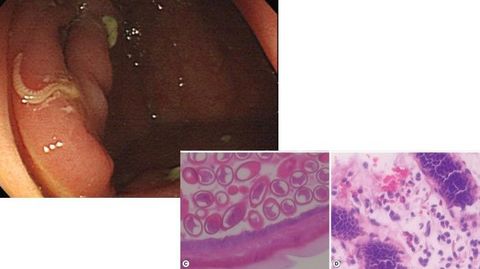

OXIURIASIS (ENTEROVIUS VERMICULARIS)

ASCARIS LUMBRICOIDES

ANCYLOSTOMA DUODENALE

NECATUR AMERICANUS

TRICHURIS TRICHURIA